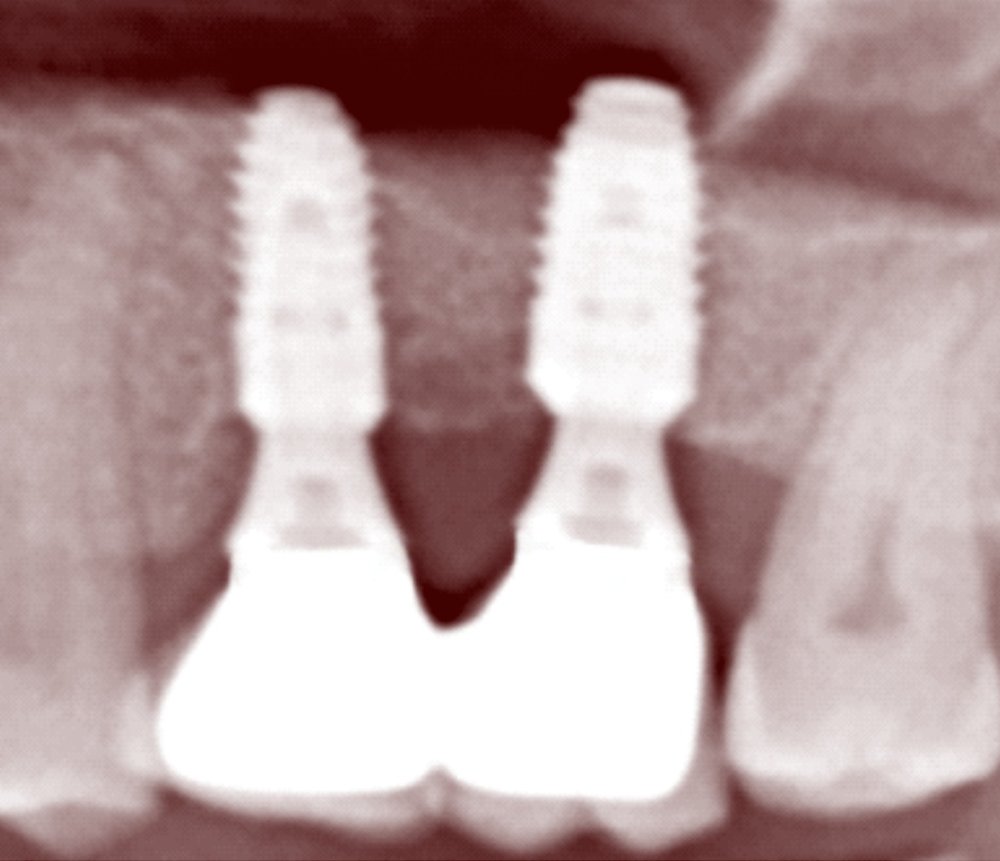

ALT DİŞLERİN TEDAVİSİ TREATMENT OF THE MANDIBULAR TEETH

2020